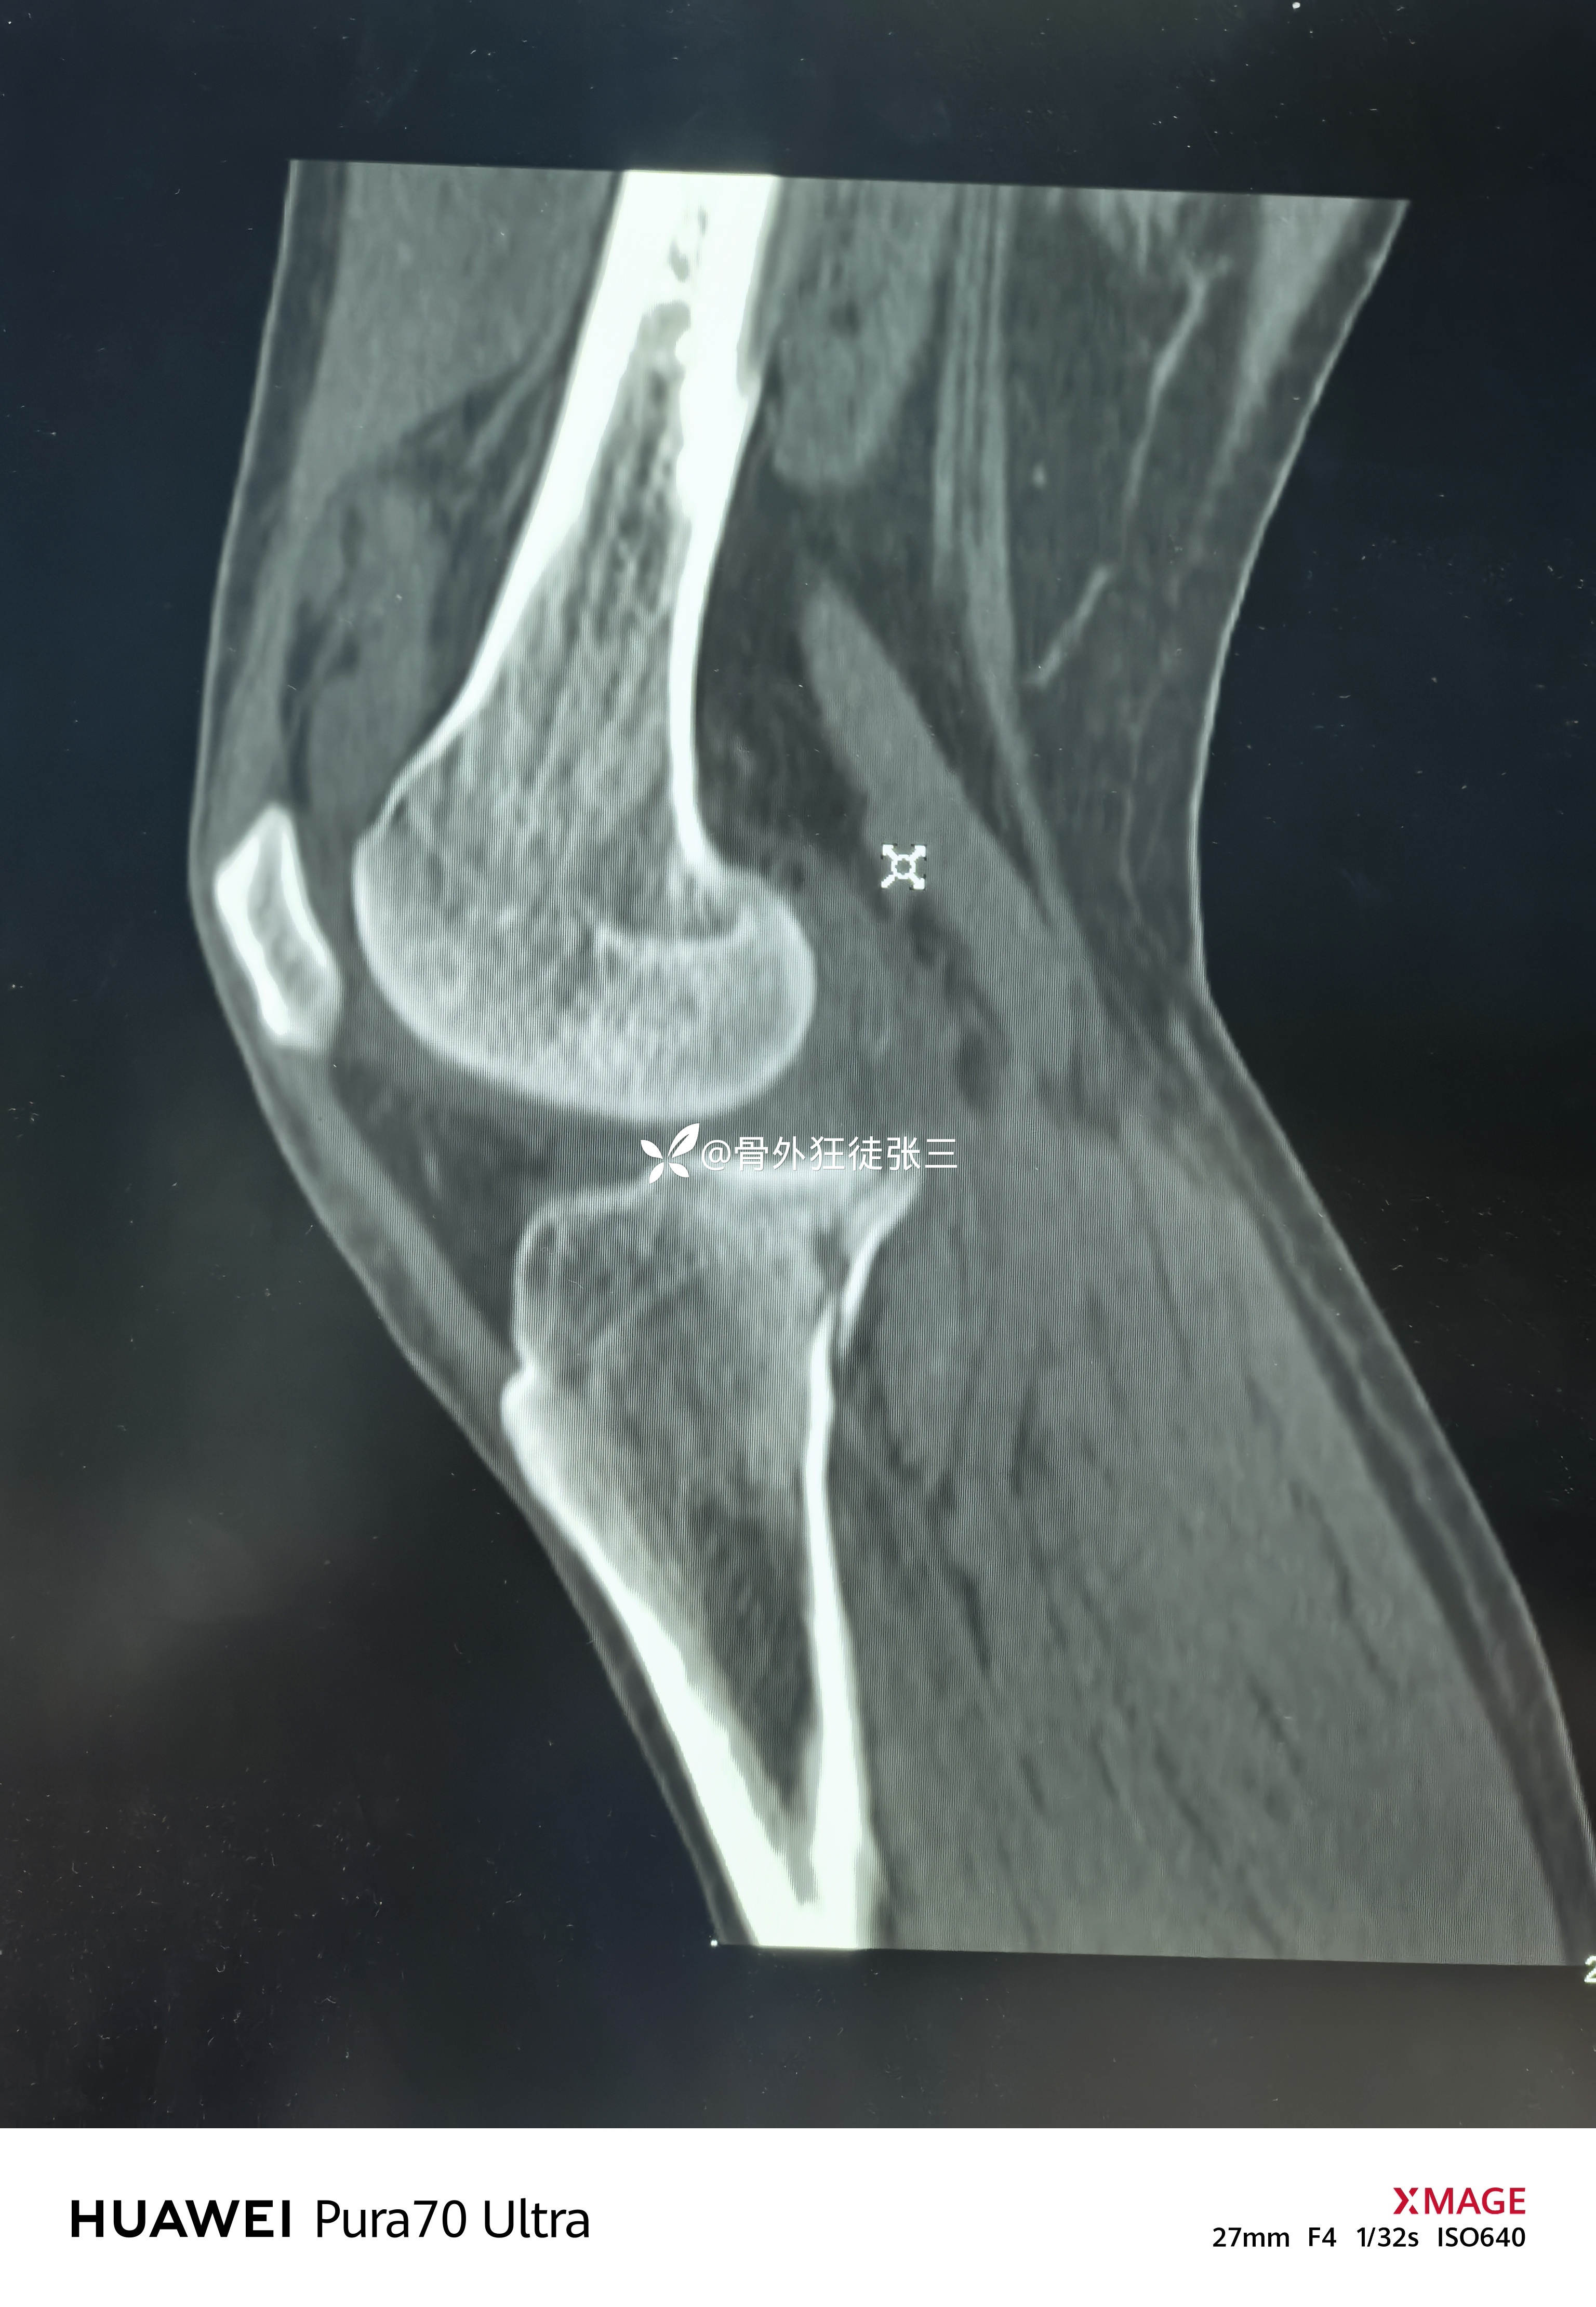

但是CT下显形惊涛骇浪

右胫骨平台骨折

(屈曲内翻型——后内侧平台骨折+外侧平台塌陷+ACL止点撕脱)